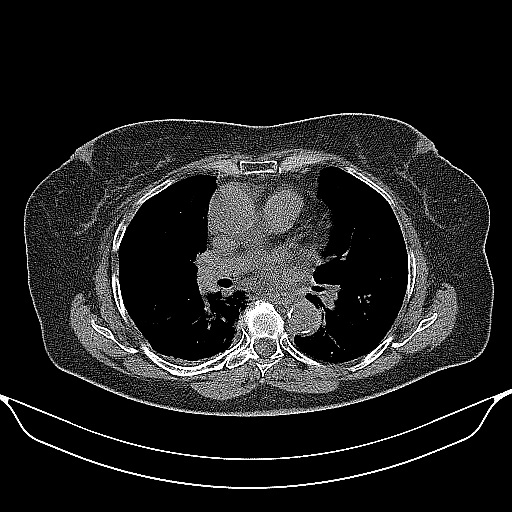

Reconstructed NATIVE CT scan (cycle consistency)

No window - Raw intensity values

Lung window (WL -600, WW 1500 β†’ Low βˆ’1350, High +150)

Mediastinum window (WL 40, WW 400 β†’ Low βˆ’160, High +240)